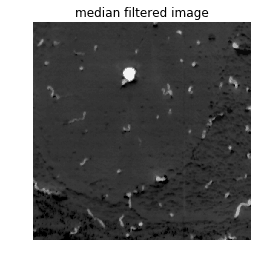

为了消除噪声,我们使用简单的中位数滤波器来移除异常值,但也可以使用一些不同的噪声去除方法或伪影去除方法。这项工件由采集系统决定(显微镜技术),可能需要复杂的算法来恢复丢失的数据。工件通常分为两类:

在分割数据之前,我们应该检查一下数据集,以确定是否存在由于成像系统而造成了伪影。在此示例中,我们仅讨论一个图像。通过查看图像,我们可以看到没有任何明显的伪影会干扰分割。但是,小伙伴们可以使用中值滤镜消除离群值噪声并平滑图像。中值过滤器用中值(在给定大小的内核内)替换离群值。

内核大小3的中值过滤器

median_filtered = scipy.ndimage.median_filter(grayscale, size=3)plt.imshow(median_filtered, cmap='gray')plt.axis('off')plt.title("median filtered image")